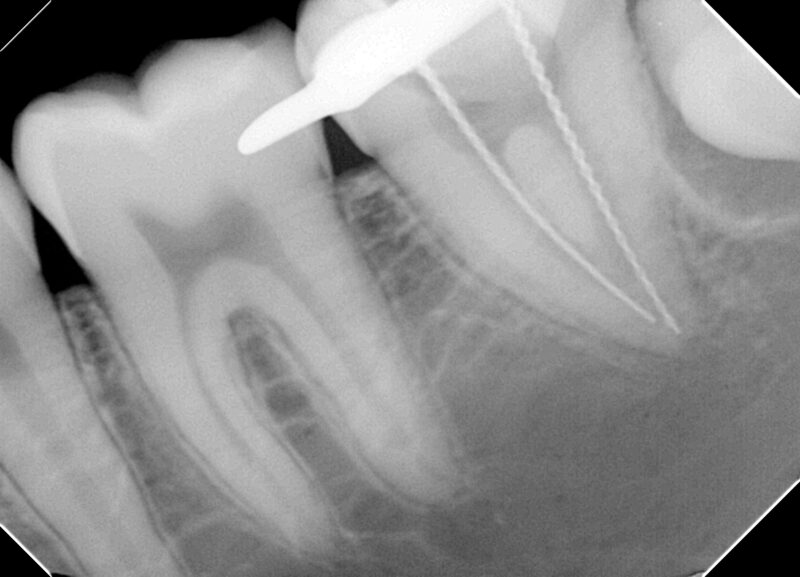

【術中マイクロ写真ならびに術中レントゲン写真】

根管内を拡大視野で確認し、出来る限り歯の切削量を減らすように治療をしています。

根の入り口は2か所、根の先端は1か所であり、歯の中で根管が合流していることが分かります。